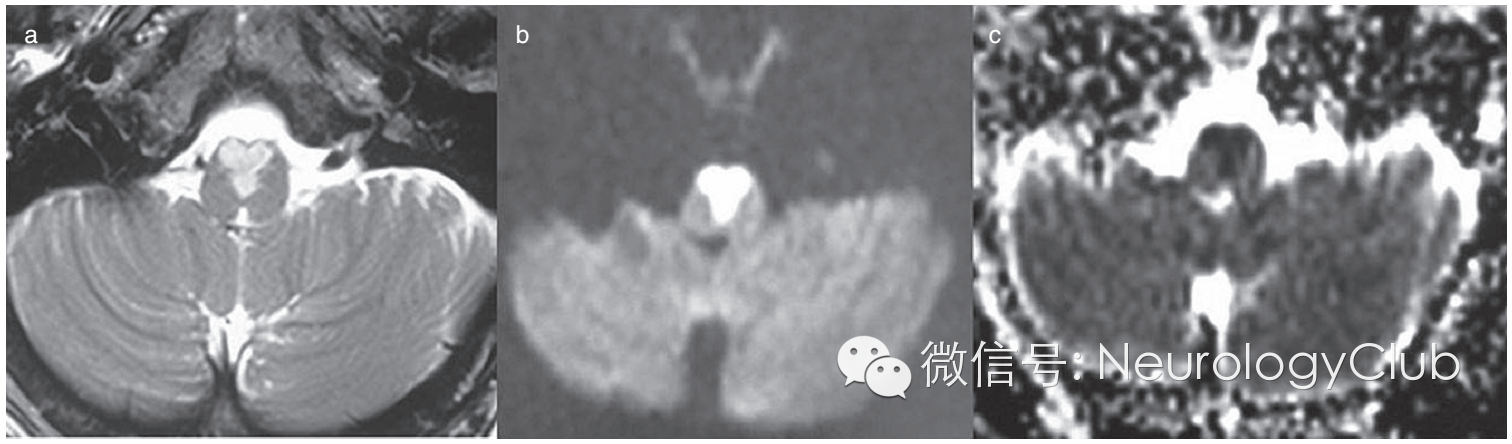

延髓内侧由椎动脉和脊髓前动脉分支供血,其中延髓内侧上1/3由椎动脉旁分支供应,下2/3由双侧脊髓前动脉及其汇合而成的前正中动脉延髓支供应。双侧延髓内侧梗死血管病理学改变以大动脉粥样硬化最为常见,其次是小穿支动脉病变,另外也有栓塞、动脉夹层、动脉炎或合并先天血管变异等病因报道。影像学特点头颅MRI检查,尤其是DWI对双侧延髓内侧梗死的早期诊断有很大的帮助。其影像学表现为磁共振显示双侧延髓内侧类似“心型”或“Y形”的长T1长T2信号影,DWI高信号,ADC低信号,符合梗死改变,具有特征性的诊断意义。

引自:Bilateral medial medullary infarction: the "heart" reveals the diagnosis.Int J Stroke.2014 Jun;9(4):E18.